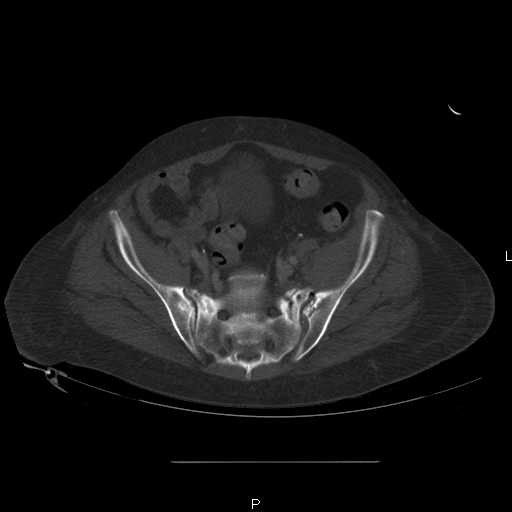

attached are images of a 59 yo female, admitted today after motor vehicle collision. Pt states her pelvis has been very painful ever since she fell on her buttocks from ground level a little over a year ago.

medical history significant for scleroderma, raynauds syndrome, and COPD. no past surgeries.

pt states she is very limited in walking ability secondary to pain. she requires a cane or a walker. friends and family do her shopping. the pain is localized primarily around left upper groin. she points to the rami region.

the question is if her medical history is contributing to the nonunions, and if anyone would consider surgical intervention, or is there some other successful intervention?